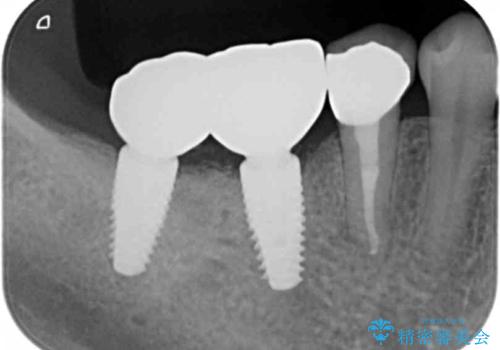

患者様のご希望により、右下大臼歯2本(右下76)のインプラント治療、右下小臼歯(右下5)の根管治療及び補綴治療を行いました。

奥歯でしっかり噛むことができるようになり、喜んで頂けました。

セラミッククラウンの審美的な仕上がりにもご満足頂けました。

インプラントの種類:ストローマン BLT

クラウンの種類:ベレッツァクラウン(右下76)、ジルコニアクラウン スタンダード(右下5)